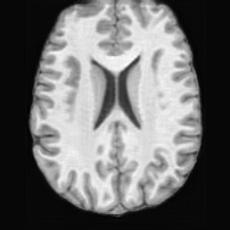

Unconditional Generation. Fig. 4 (a) presents examples of paired lesion masks and brain images generated by USB. Notably, although the paired lesion-brain generation begins unconditionally from random noise, USB produces lesion masks exhibiting diverse locations, sizes, and shapes, while simultaneously generating anatomically coherent brain images with embedded pathological patterns that spatially correspond to the generated lesions within each pair.

In Tab. 1, we present the first quantitative benchmark evaluation of both generation tasks. For the unconditional generation task, we generated 256 paired lesion–brain samples for each lesion type (stroke and WMH). For the conditional generation task, we used masks from the ATLAS and ISLES test sets as stroke lesions, and masks from the ADNI test set as WMH lesions. Notably, for each lesion type, the unconditional generation achieved superior quantitative performance, highlighting that the paired diffusion mechanism effectively generates coherent lesion-brain pairs through joint modeling between USBbrain and USBlesion. Additional generation results are provided in Suppl. A.